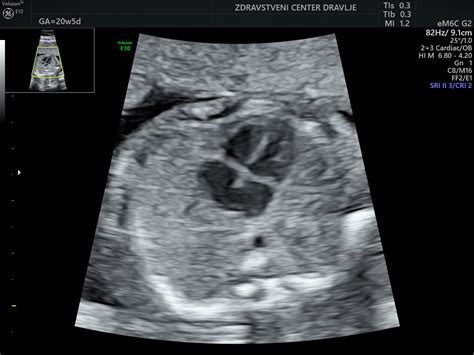

Na ultrazvoku v 23. tednu nosečnosti je mogoče opaziti, da se otročku oblikujejo majhne bradavice. Obrazek ima že skoraj popolnoma izoblikovan - potrebuje le še malo maščobe, da se izpopolni. Otroček se zabava s poslušanjem vašega glasu in srčnega utripa, sliši lahko celo nekaj glasnih zvokov iz zunanjega sveta, kot so avtomobilske hupe in pasji lajež. Spol otroka je zdaj jasno prepoznaven. Če je vaš otrok deklica, ima jajčnike že nekaj tednov, njena nožnica pa je zdaj votla. Če je fantek, že ima penis in prostato. V tej fazi otrokova koža še vedno ostaja prosojna in se zdi, kot da mu je malce prevelika. To je zato, ker raste hitreje kot njegovo telo, ki jo nato s kopičenjem maščob in rastjo dohiti.

V vašem primeru se pojavljajo posebna vprašanja glede oblike poroda, predvsem zaradi preteklosti in trenutne velikosti ploda. Prvi otrok je bil ob porodu težak 4560g, kar je že samo po sebi predstavljalo izziv. Dodatno so vas pestili prekomerna plodovnica, diastaza trebušne mišice (ki ste jo sicer uspeli sanirati na razmak enega prsta, a je ostala "luknjica" z vidnim premikanjem črevesja v predelu popka) in travmatičen porod z uporabo epiduralne analgezije, ki je povzročila začasno ohromelost. Kljub odsotnosti sladkorne bolezni v nosečnosti, se v 23. tednu nosečnosti ponovno kaže, da plod prehiteva v rasti in ima že skoraj 700g.